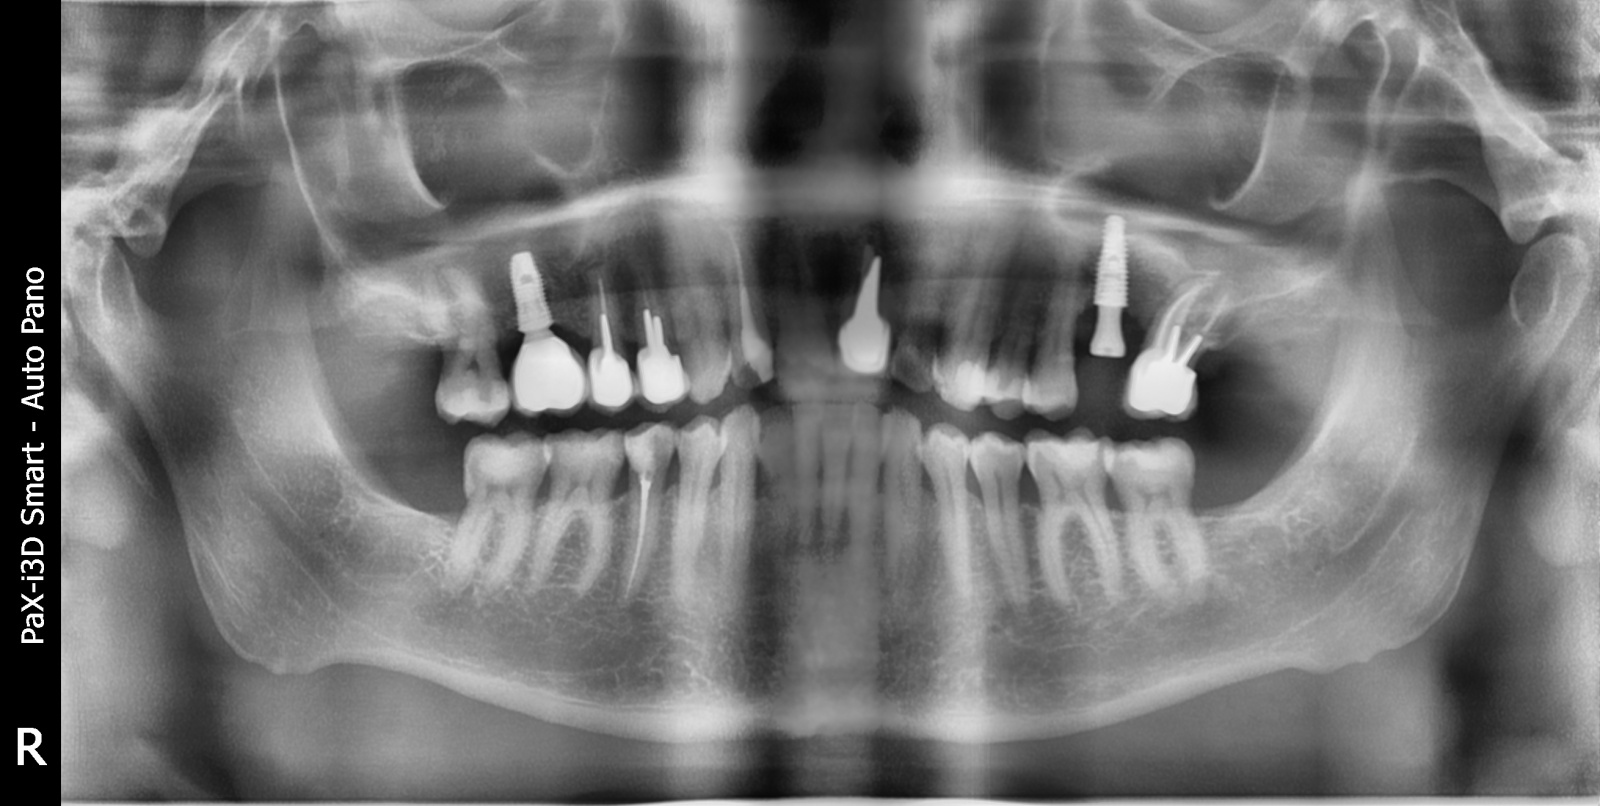

Это мой коллега Андрей переделывал за уважаемой чешской клиникой